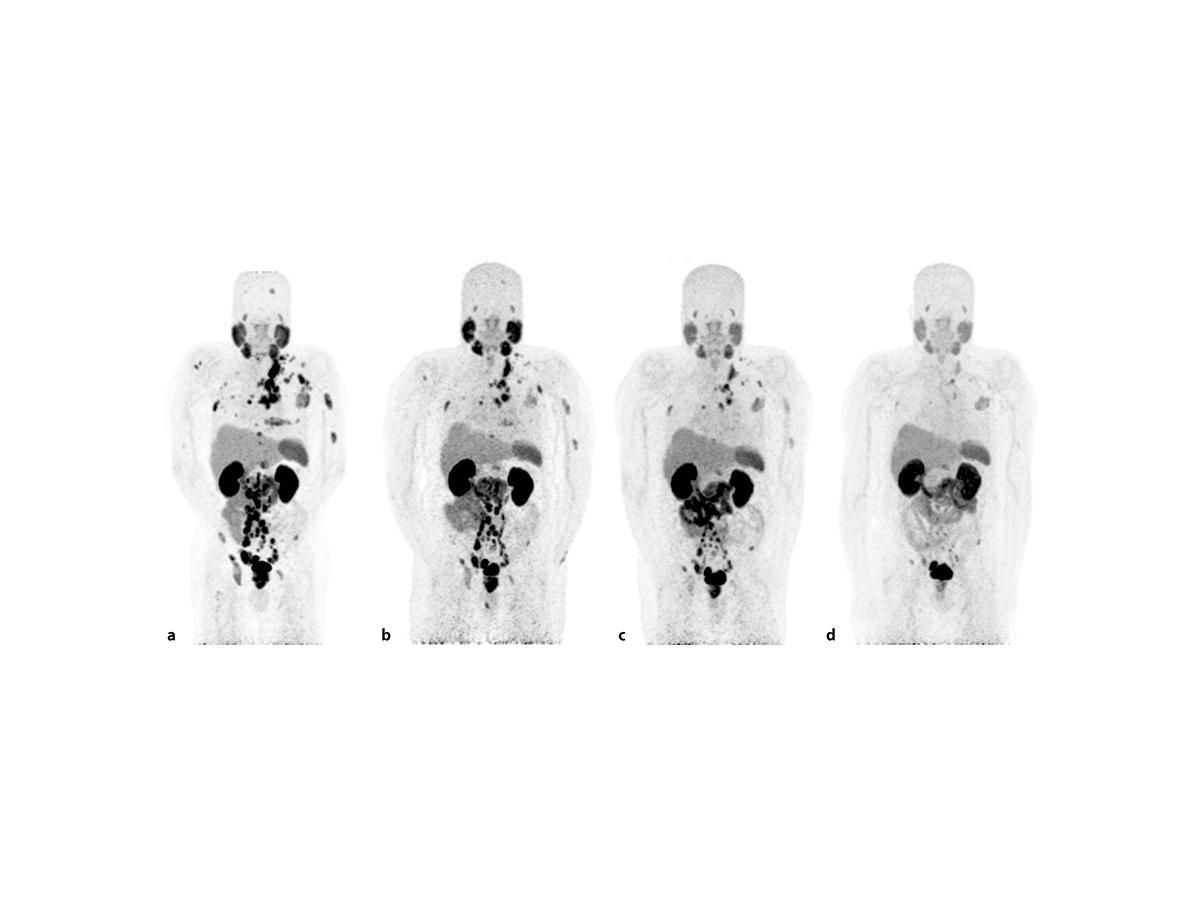

Пэт псма что это

Пэт псма что это 104 фотографий